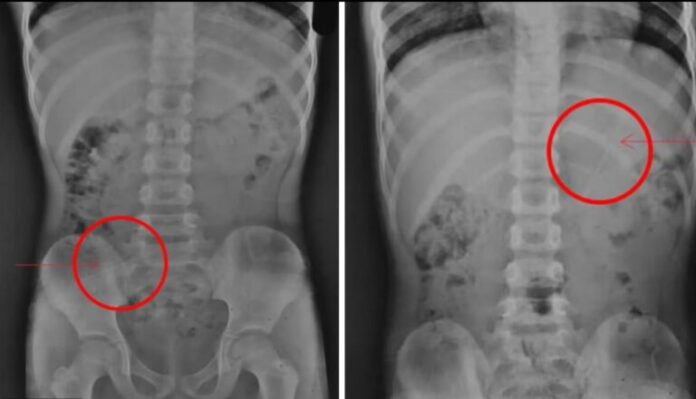

Um menino, 7, sobreviveu após engolir acidentalmente um lápis de 10 centímetros. O caso aconteceu no Nepal. No hospital, os médicos fizeram radiografias no menino.

Não há informações de como o menino engoliu o lápis. A criança não precisou passar por cirurgia e ficou sem ferimentos. A imagem do tórax do menino mostrou que o lápis estava no estômago dele. De acordo com as informações, o menino ficou em observação, podendo comer apenas banana e beber bastante líquido.

A criança ficou na espera por novos exames, mas a mãe revelou que o filho evacuou o lápis. Ele recebeu alta no dia seguinte.